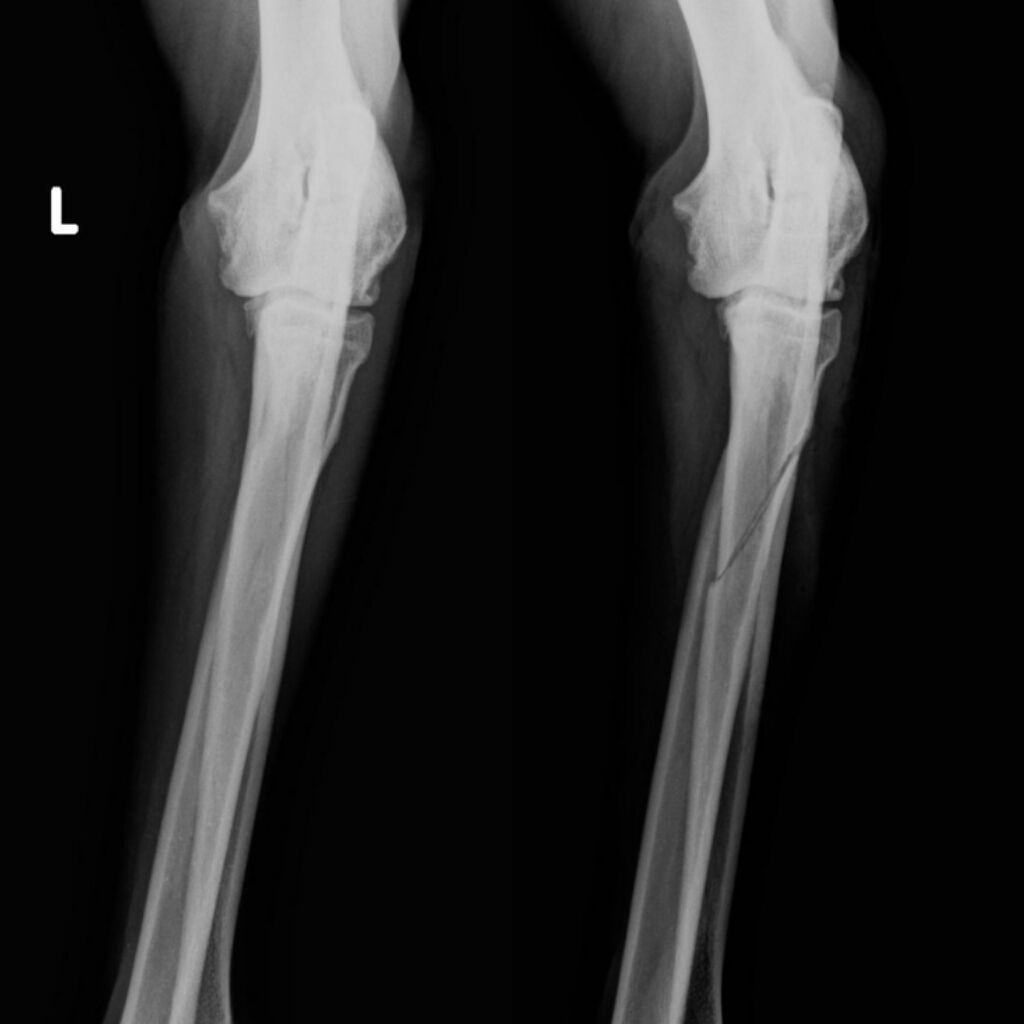

Esaminiamo come viene articolato il percorso riabilitativo e quali sono le possibili complicanze. Le fratture intertrocanteriche generalmente incrociano nella zona tra il piccolo trocantere e il grande trocantere (sporgenza ossea che si può sentire sotto la pelle sulla parte esterna dell'anca) dove si inseriscono altri muscoli.

Il femore è l'osso più lungo, voluminoso e resistente dello scheletro umano. Operata 4 giorni dopo, le applicano un basic nail. Il 4 luglio scorso ho avuto un incidente in bici, con frattura pertrocanterica composta del femore sinistro.

L'estate scorsa durante una gara mi sono fratturato il femore dx (frattura pertrocanterica), mi hanno messo una placca e fin qui tutto ok.

Al momento ho un gran blocco psicologico in quanto non trovo giustificazione a quanto accaduto essendo caduto praticamente sul nulla! Frattura sottocapitata frattura collo femore frattura pertrocanterica frattura sottotroncaterica. Il femore è l'osso più robusto e voluminoso dell'intero apparato scheletrico umano, la cui lunghezza corrisponde mediamente ad oltre il 25% della statura dell'individuo. Questo femore è l'osso più forte e più lungo dell'intero scheletro. Questi includono, ad esempio, la frattura pertrocanterica del femore, la frattura pelvica anteriore e la frattura dell'articolazione dell'anca (frattura di pipkin). Frattura pertrocanterica femore trattata con chiodo intrauma elos intrauma cephalomedullary nail. Caduta praticamente da fermo, nessuna abrasione da sfregamento e pantaloncini intonsi. Want to learn more about it? Barbero s con aiuto del dott. Frattura pertrocanterica del femore con minimo 3 mesi di stop. Articolandosi nella sua estremità prossimale con l'osso dell'anca dà origine all'omonima articolazione. L'estate scorsa durante una gara mi sono fratturato il femore dx (frattura pertrocanterica), mi hanno messo una placca e fin qui tutto ok. Mia madre ha subito la frattura pertrocanterica del femore, in seguito ha subito intervento di sintesi con chiodo endomidollare fixion pfn i primi di novembre c.a. L'aumento dell'età media della popolazione (oggi oltre 80 anni) ha portato a un aumento di tali fratture in anziani, che spesso sono associate ad altre patologie internistiche che possono portare a complicanze nel decorso. Correva 18 gennaio, con 35 anni sulle spalle. La frattura pertrocanterica, come altre fratture a carico del femore, è molto frequente negli anziani. Febbraio 2016, mia madre cade in casa e si frattura il femore sx (frattura pertrocanterica).